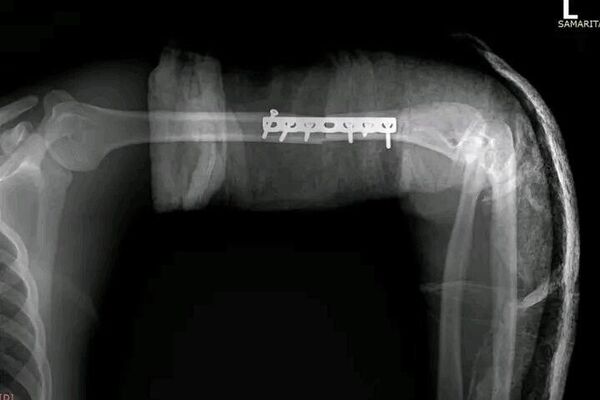

ሳምሪታን ቀዶ ሕክምና ማዕከል ለመጀመሪያ ጊዜ በማሽን የተቆረጠ እጅን በተሳካ ሁኔታ መቀጠል መቻሉን አስታወቀ

የማእከሉ የአጥንት ቀዶ ሕክምና የከፍተኛ አደጋዎች እና መገጣጠሚያ ቅየራ ሰብ-ስፔሻሊስት ዶ/ር ቢኒያም ተሾመ፣ በኢትዮጵያ ውስጥ የተቆረጠ እጅን ለመቀጠል የተደረጉ የቀዶ ሕክምናዎች አለመኖራቸውን ለአገር ውስጥ የግል ሚዲያ ተናግረዋል፡፡

አደጋው የደረሰው የሥጋ ማሽን ለማስተካከል ይሞክር በነበረ የ20 ዓመት ወጣት ላይ ነው፡፡

"እጁን ሙሉ በሙሉ ቆርጦትም አልቆመም፣ ደረቱን ቀዶታል፣ ወደ ውስጥ አለመግባቱ ነው እንጂ የደረቱ ጉዳት ከፍተኛ ነበር የሚሆነው።" ሲሉ ሐኪሙ የጉዳቱን ሁኔታ አብራርተዋል፡፡

ተጎጂው በፍጥነት ወደ ጤና ተቋም መሄዱ፣ ጤና ተቋሙም የሚፈሰውን ደም አስቁሞ የተቆረጠውን እጅ በረዶ ውስጥ ማስቀመጡ ዳግም ለመቀጠል ወሳኝ እርምጃ መሆኑ ተገልጿል።

6 ሠዓት የወሰደው ቀዶ ሕክምናው በስኬት ቢጠናቀቀም ቀጣይ የሕክምና ከትትሎች አስፈላጊ መሆናቸውንም ሐኪሞቹ ጠቁመዋል፡፡